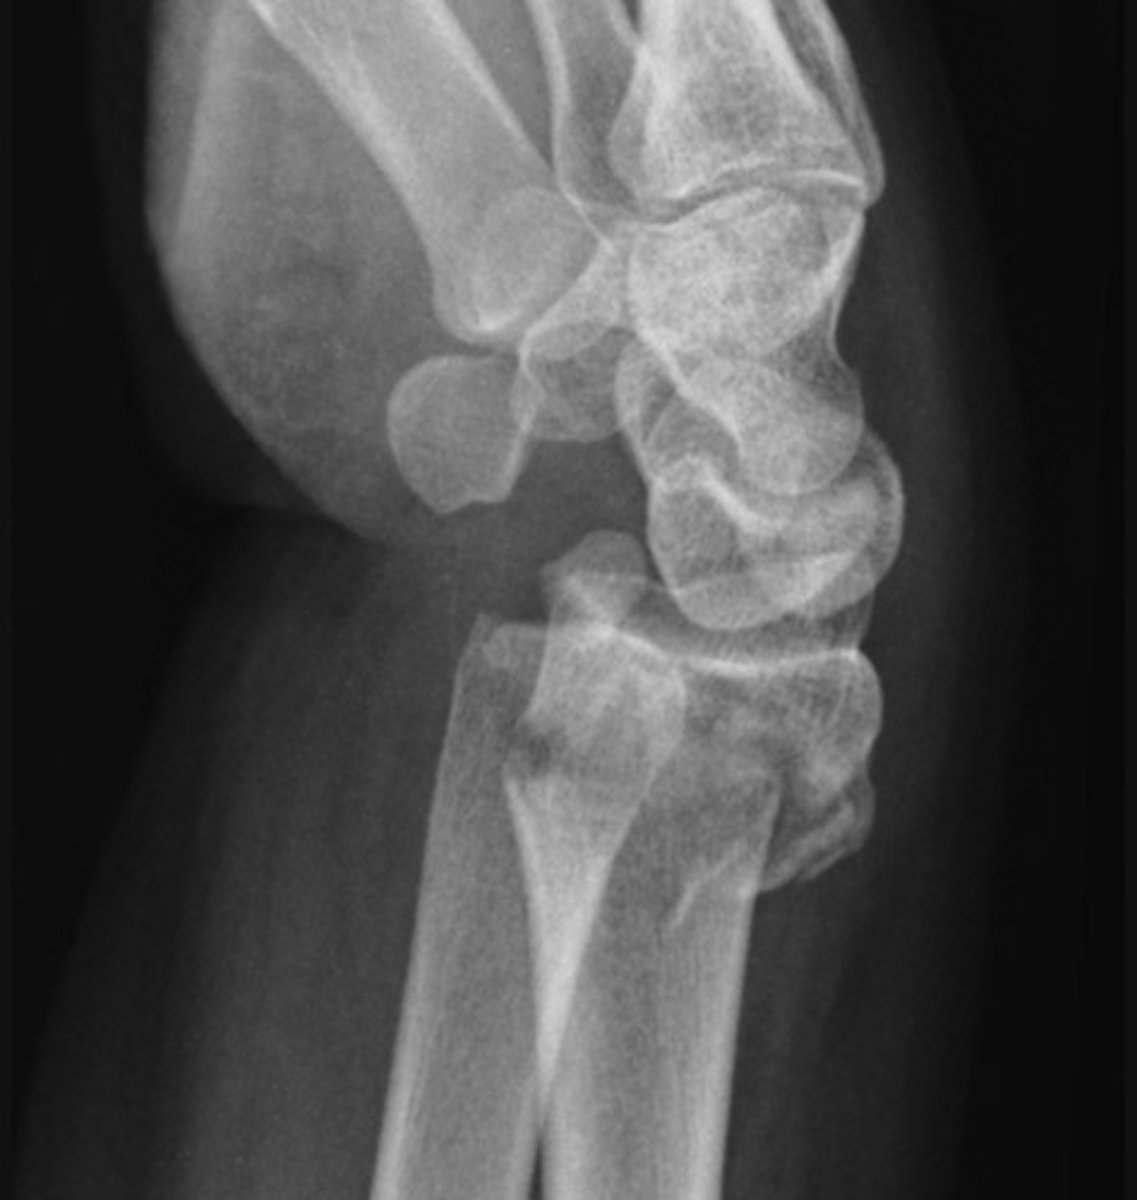

Monteggia fracture-dislocation - Lateral

a fracture of the ulnar shaft with dislocation of the radial head at the elbow

The radiocapitellar line should pass through the middle of the capitulum of the humerus